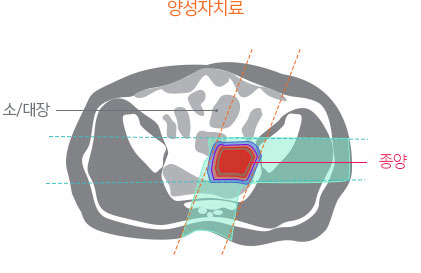

양성자치료는 방사선 재 치료 또는 고선량 치료로 인한 부작용에 대한 우려를 낮추면서 충분한 방사선량을 전달하여 높은 종양 제어율을 얻을 수 있습니다.

이미 방사선치료가 시행된 재발 직장암의 경우 종양 제거가 어렵고, 수술의 경우 미용적, 기능적 제한이 큰 것으로 알려져 있습니다. 따라서 고선량의 방사선 재 치료가 시행되는 경우가 많은데, 이 경우 세기조절 방사선치료를 시행하더라도 주변 정상 장기에 노출되는 방사선으로 인한 부작용이 흔하며, 총 방사선량이 제한되어 5년 종양 제어율이 50% 이하로 알려져 있습니다. 하지만 주변 정상 장기에 방사선 노출을 크게 낮출 수 있는 양성자치료는 부작용에 대한 우려를 낮추면서 고선량의 방사선을 전달하여 종양을 제거할 수 있을 것으로 기대하고 있습니다.

직장암 환자에서 양성자치료에 대한 임상 결과는 아직 드문 상황입니다. 하지만 양성자치료와 유사한 특성을 가진 입자선 치료 결과를 보면 90% 이상의 장기 종양 제어율이 보고된 바 있습니다.